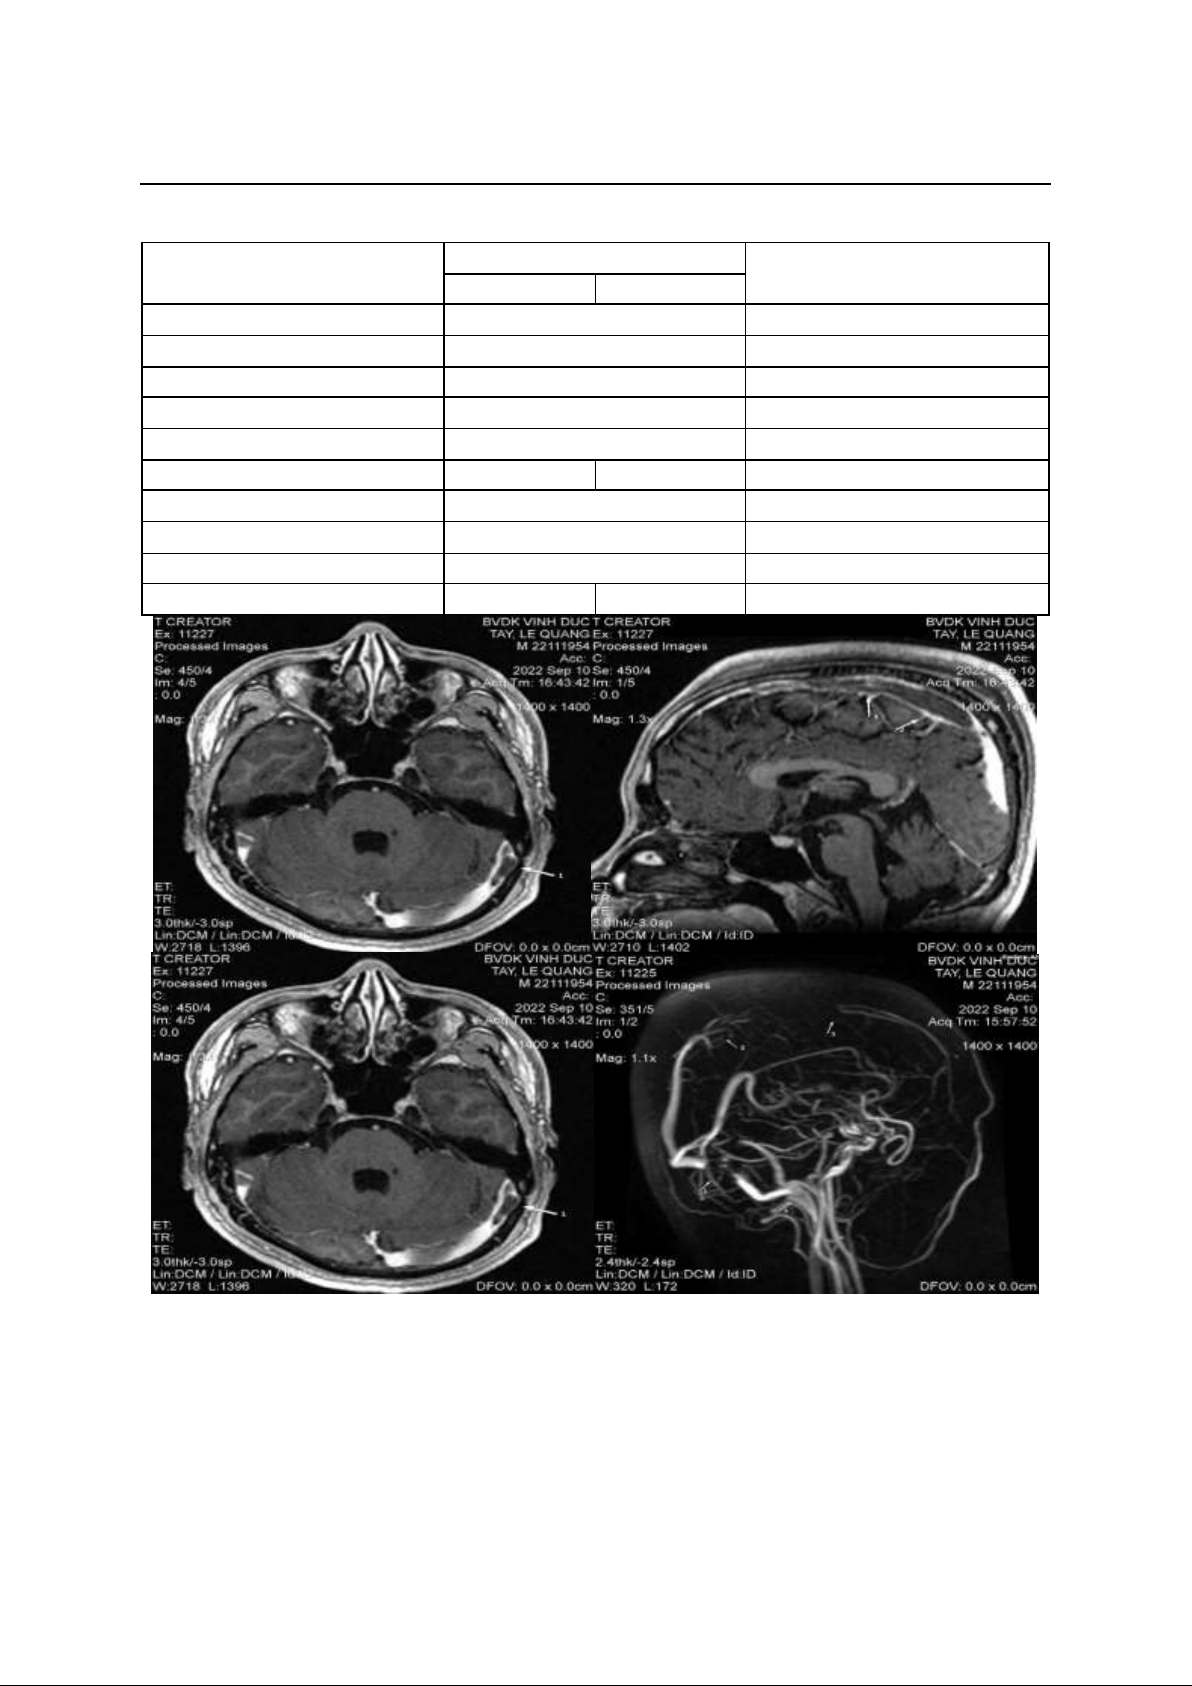

Hình ảnh MRI não

MRI não cho thấy huyết khối nhiều xoang

tĩnh mạch não. Hàng trên: (a) Huyết khối bán

phần xoang ngang trái. (b) Huyết khối bán

phần xoang sigma trái. Hàng dưới: (c) Huyết

khối bán phần xoang tĩnh mạch dọc trên. (d)

Huyết khối bán phần và hoàn toàn xoang tĩnh

mạch dọc trên (mũi tên 2, 3); huyết khối

hoàn toàn xoang ngang trái (mũi tên 1) và

huyết khối bán phần xoang sigma trái (mũi

tên 4)